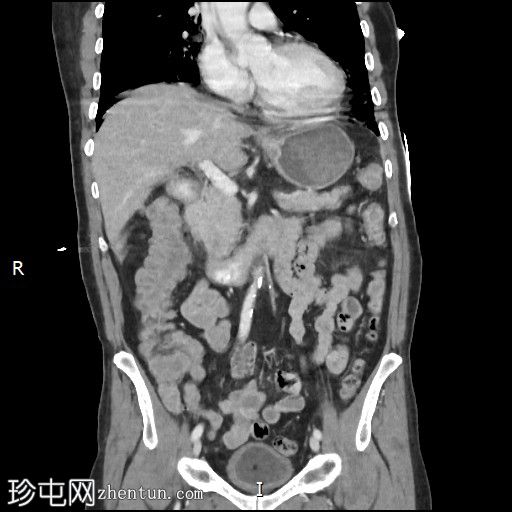

冠状位增强扫描

动脉期

门静脉期